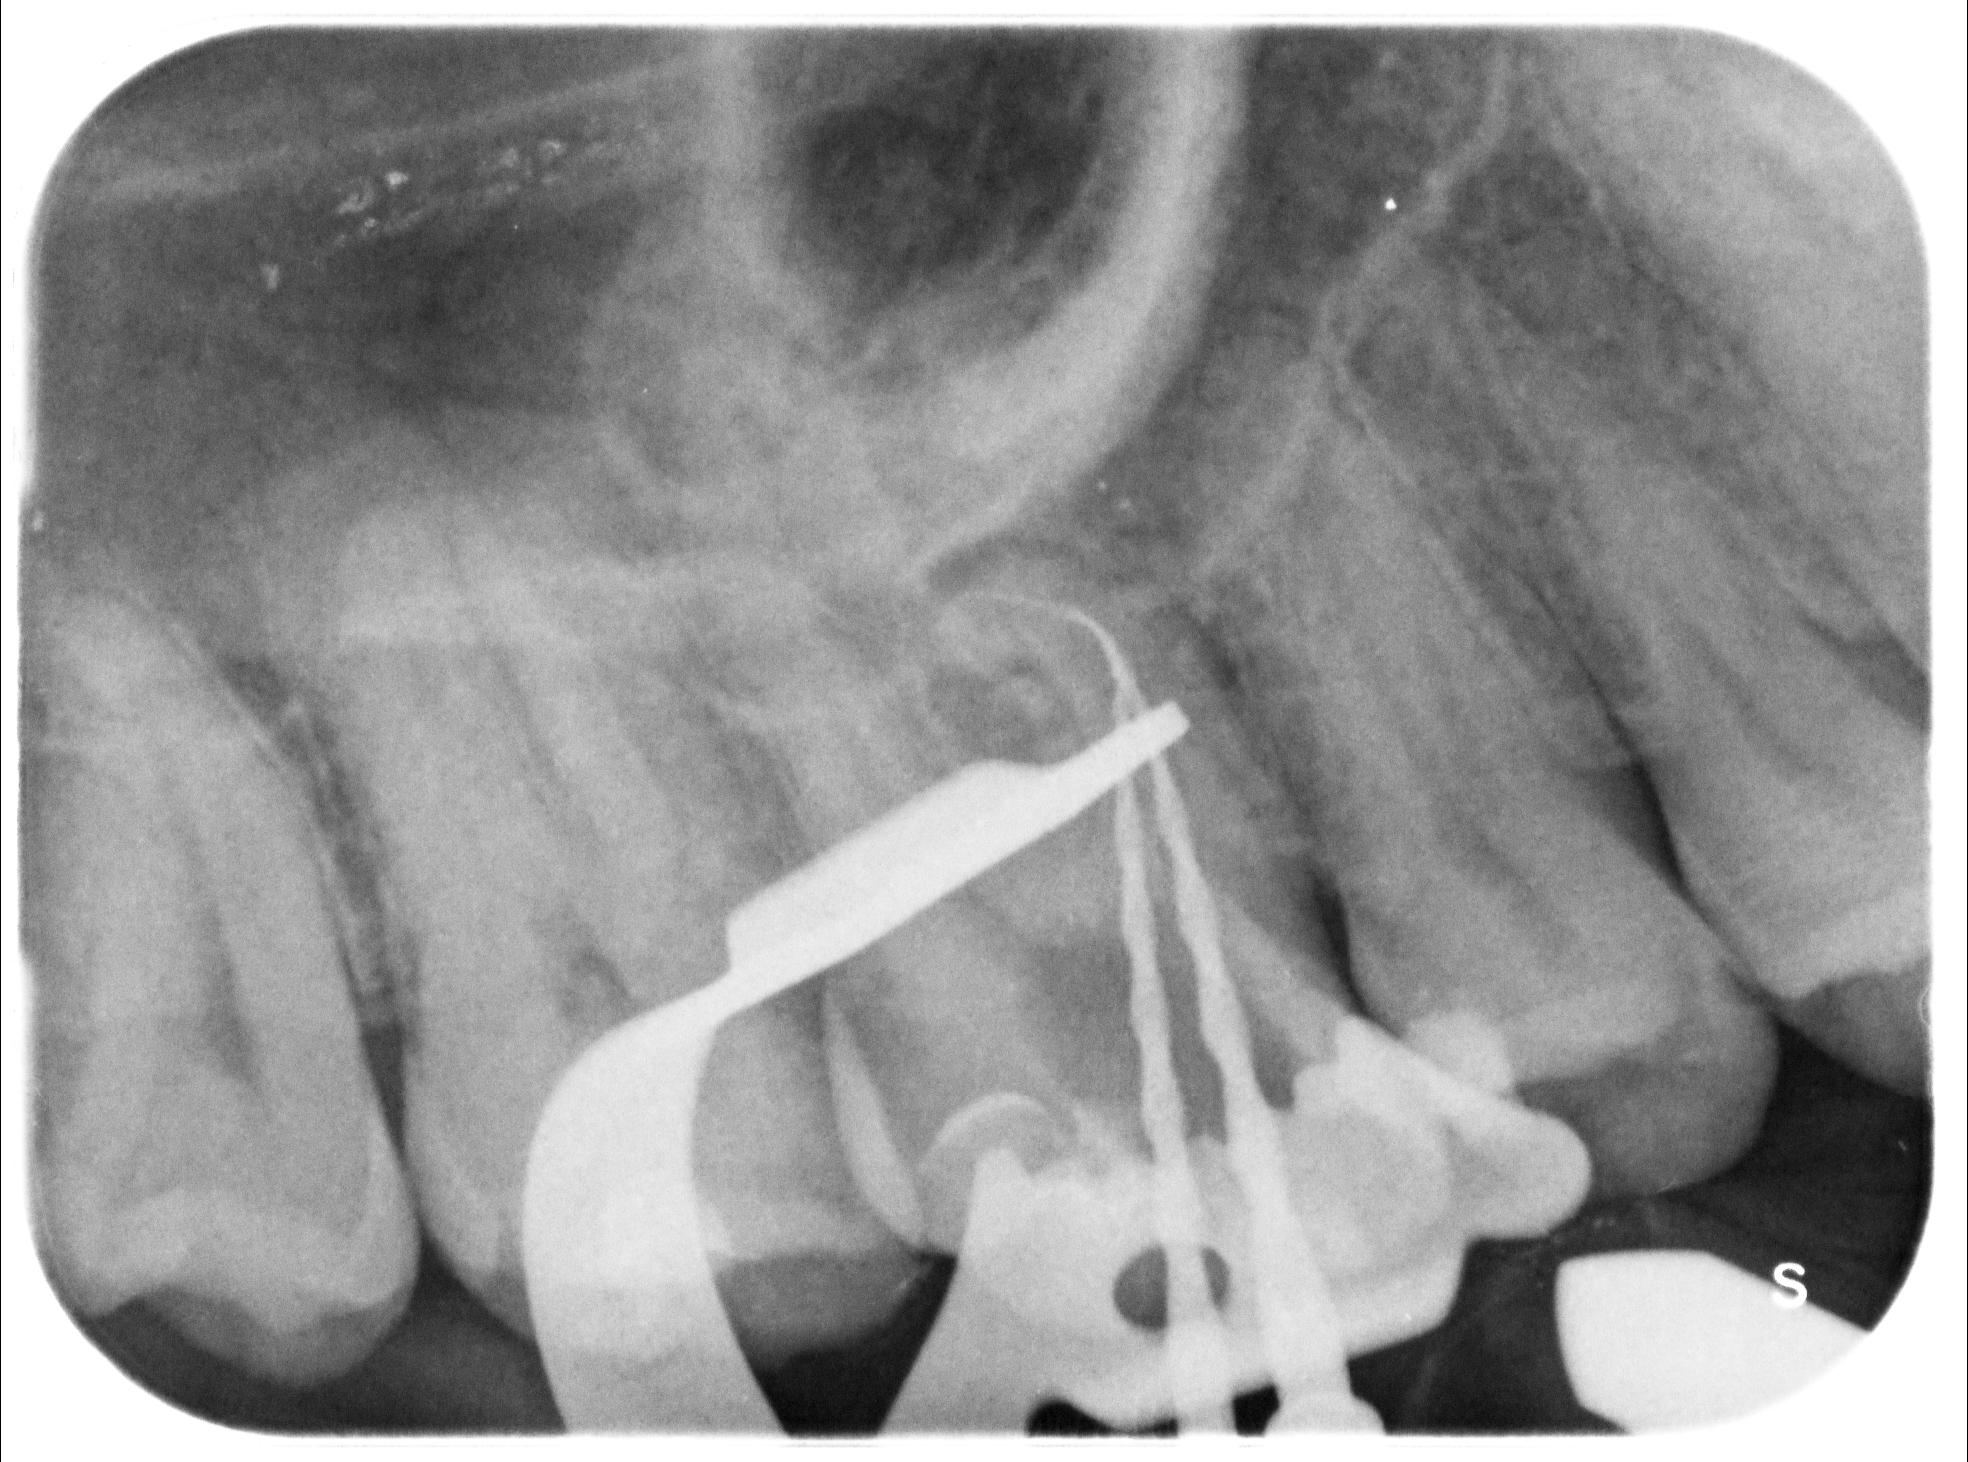

ENDODONZIA

Caso clinico – ritrattamento ortogrado di 1° molare inferiore con lesione

Caso clinico – trattamento ortogrado di 2° molare inferiore